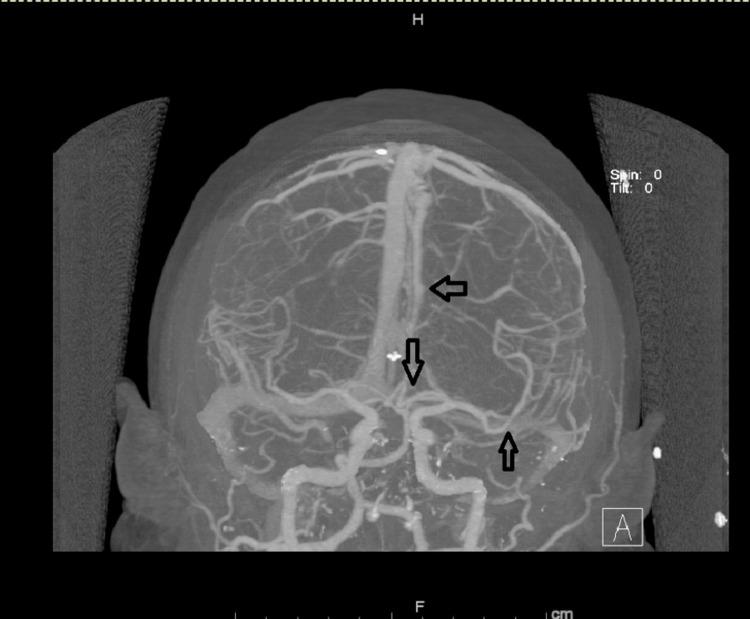

Reversible cerebral vasoconstriction syndrome (RCVS) is not an uncommon condition. It should be suspected in young patients with new onset headaches and neurologic deficits. We report a 38-year-old male patient with a history of depression on desvenlafaxine for two years and no other triggering factor who was diagnosed with RCVS confirmed by cerebral angiogram. Discontinuation of the medication and calcium channel blockers initiation led to rapid clinical improvement. The diagnosis was further confirmed by angiographic improvement two months later. Although the association of selective serotonin reuptake inhibitors (SSRI)/ serotonin norepinephrine reuptake inhibitors (SNRI) with RCVS has been reported frequently, desvenlafaxine is a much less reported trigger, with only nine cases in total. In contrast to prior reported cases where the time from exposure to onset of RCVS was weeks to months, the time interval, in this case, was two years. This case report aims to support previous literature in suggestion of this association.

可逆性脑血管收缩综合征(RCVS)并非罕见疾病。对于新发头痛和神经功能缺损的年轻患者,应怀疑患有此病。我们报告一例38岁男性患者,有两年服用去甲文拉法辛治疗抑郁症的病史,无其他诱发因素,经脑血管造影确诊为RCVS。停用该药物并开始使用钙通道阻滞剂后,临床症状迅速改善。两个月后的血管造影改善进一步证实了诊断。尽管选择性5-羟色胺再摄取抑制剂(SSRI)/5-羟色胺去甲肾上腺素再摄取抑制剂(SNRI)与RCVS的关联已被频繁报道,但去甲文拉法辛作为诱发因素的报道要少得多,总共仅有9例。与之前报道的病例中从接触药物到RCVS发病的时间为数周至数月不同,本病例的时间间隔为两年。本病例报告旨在支持先前文献中关于这种关联的提示。